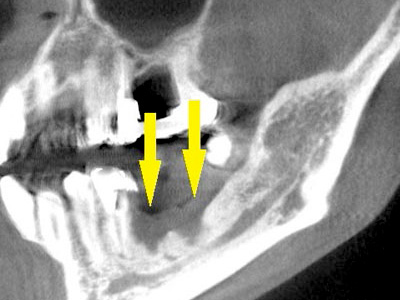

CTで見ると、骨吸収の様子が良く分かり、下顎骨の中を通る神経近くまで骨がありませんでした(黄色矢印)。

さらに、CTで別な方向から見ると、黄色矢印のように骨が吸収されていて、緑色矢印で示される神経の通る管に迫り、インプラントが埋入できるような骨量はありませんでした。